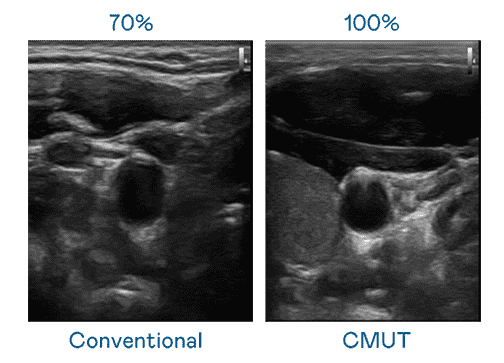

CMUT 技术是一种用电容式微机电元件来产生超音波讯号的技术。。。。与传统 PZT 压电式技术相比,,CMUT 频宽增加 30%,,,更宽频的超音波讯号让影像解析度大幅提升,,是实现高影像品质医疗超音波扫描、、、促进精准医疗发展的关键技术。。。。

大频宽带来超清晰影像

超音波影像的解析度高低,,,首先取决于探头能发出的讯号频宽。。YAXIN111 CMUT 可提供高清晰的超音波讯号,,,提供高频宽、、高灵敏度、、影像纹理细节更高的超音波影像,,协助医护人员缩短影像判读时间及利用精准的医疗影像进行诊断。。。